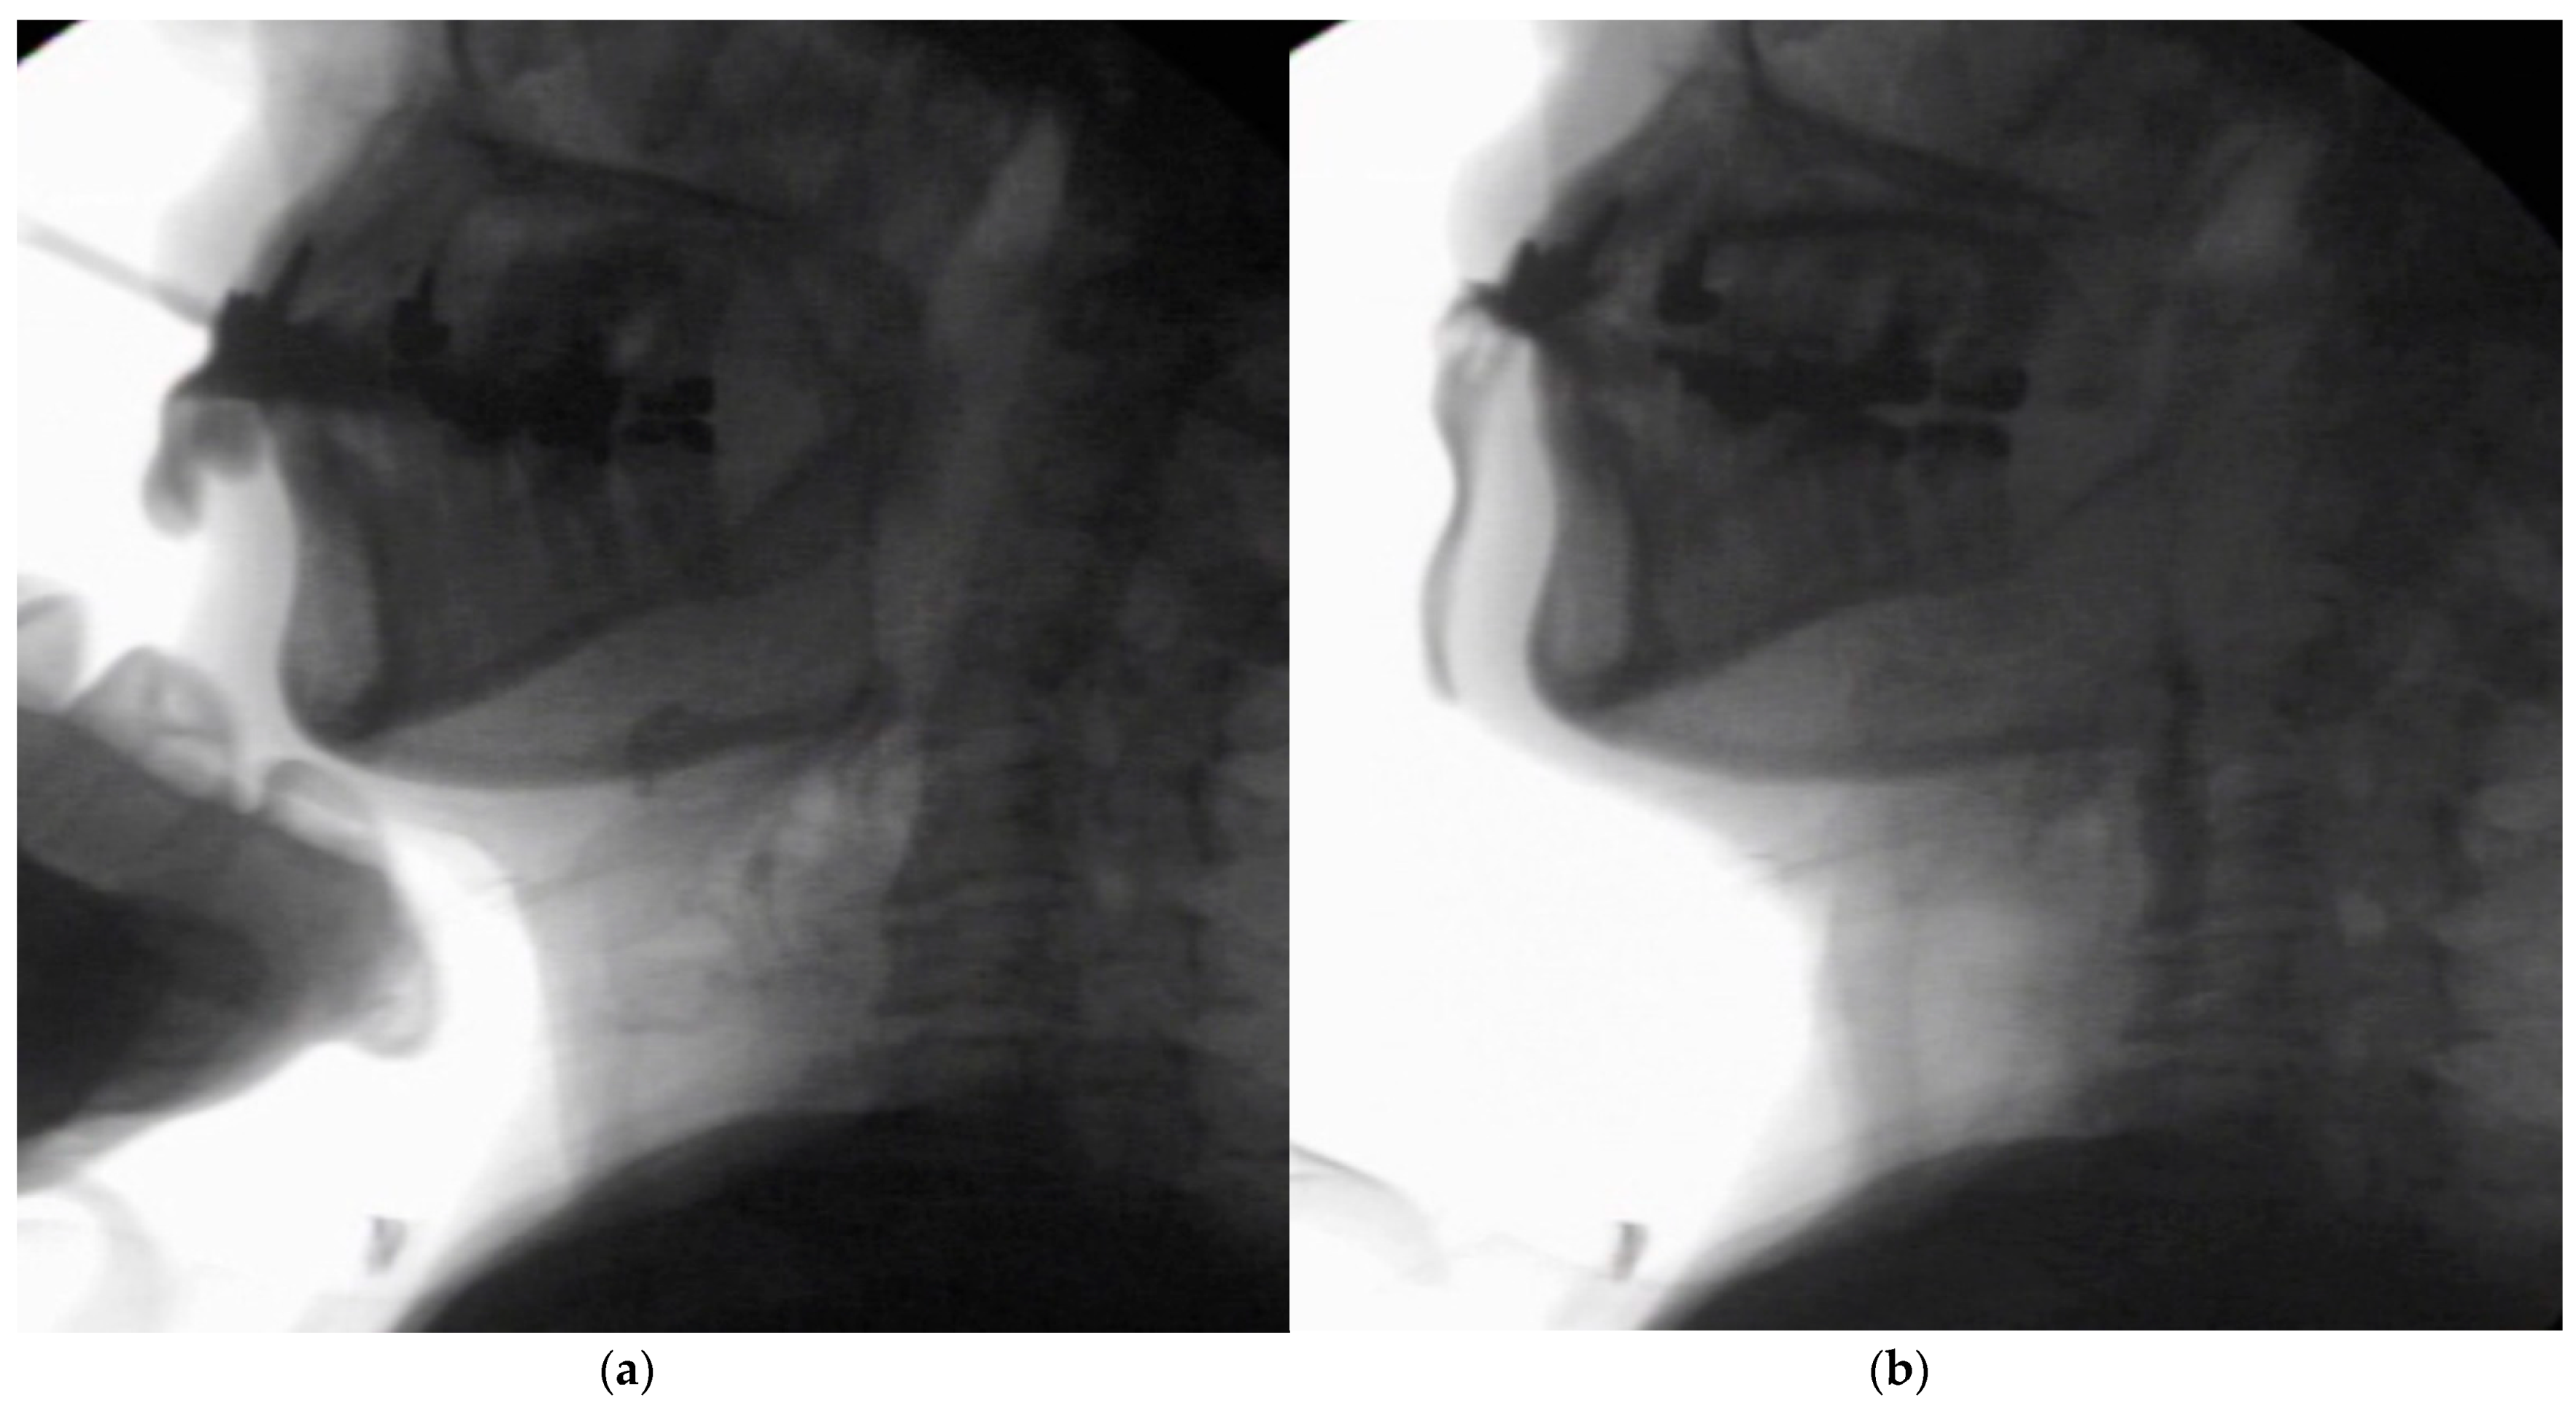

In the seated position, spoon-feeding was infeasible and bolus transport did not occur; furthermore, anterior–posterior tongue movement caused most of the food to dribble out of her mouth. After placing food on top of her tongue using a tube-fitted syringe, most still dribbled out of her mouth (Figure 1a); however, a proportion was transported into the pharynx (Figure 1b). Furthermore, after placing food at the back of her tongue with the patient reclined at 30°, a small amount still dribbled out of her mouth; however, the patient could swallow without aspiration (Figure 2). After increasing the amount placed in her mouth at one time to 7 mL, more food dribbled out of her mouth (Figure 3); additionally, there was a decreased amount transported to the pharynx. When 5 mL of a moderately thick paste was placed in her mouth, none of it dribbled out; however, slight silent aspiration was present (Figure 4). There were no particular issues observed due to peristalsis from the upper esophagus to the stomach.

Figure 1.

(a) Videofluoroscopic examination of swallowing (VF) with the patient sitting up. The test food was 5 mL of an extremely thick paste. Most of the food dribbled out of her mouth, with only a small amount being transported to the pharynx. (b) Maximum hyoid elevation upon deglutition.